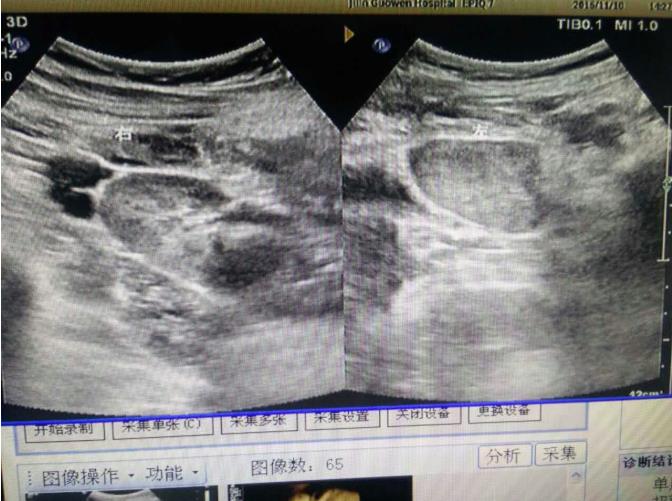

為該患常規(guī)檢查臍帶入口時發(fā)現(xiàn)臍帶入口位于胎盤下緣邊緣,胎兒超聲檢查無陽性發(fā)現(xiàn)。常規(guī)掃查右卵巢時,發(fā)現(xiàn)右卵巢旁可見腎臟回聲(正常情況下,右卵巢旁是不會掃查到腎臟回聲的),大小、形態(tài)如常,CDFI:腎內(nèi)血流灌注尚可,故囑患者左側(cè)臥位,顯示孕婦右腎位置、大小及形態(tài)正常,囑孕婦右側(cè)臥位,發(fā)現(xiàn)脾臟下方無腎臟回聲,故考慮該患左腎游走腎。該患于2016年12月2日復(fù)查,結(jié)果如前。